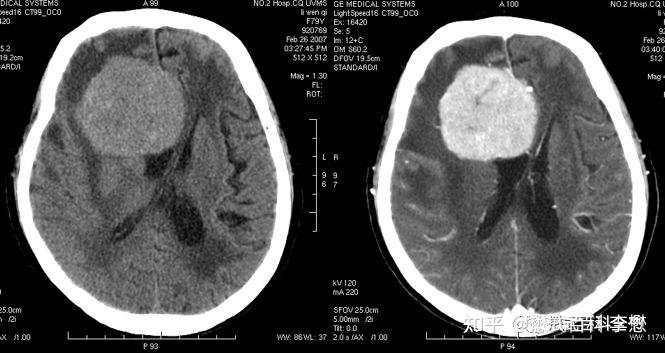

如图所示,左边是CT平扫,右边是CT增强扫描。可以发现肿瘤组织明显强化,在图像上更白了。

所以,CT平扫和CT增强结果相差大不大,主要取决于组织对于碘剂的摄取。如果摄取多了,那么强化就明显,其增强与平扫的差别就很大。